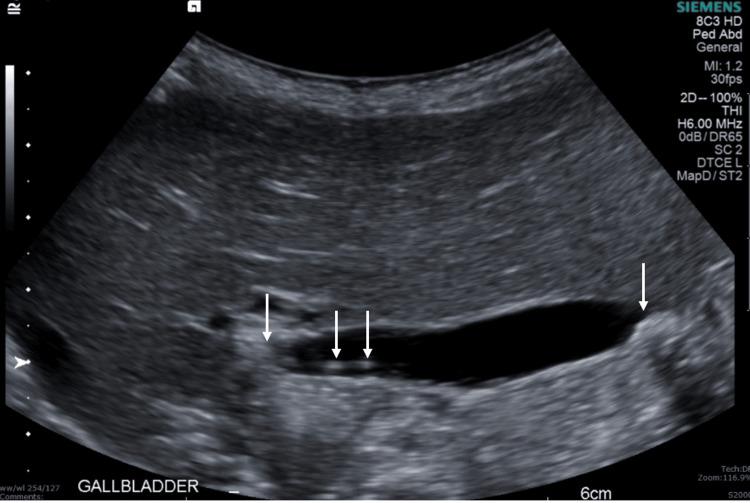

Cholelithiasis, or gallstone(s), is a leading cause of healthcare utilization in the United States. It is more common in adults but can occur in the pediatric population as well. The following is a case report of choledocholithiasis in a 19-month-old girl. A 19-month-old girl with abdominal pain presented to the emergency department (ED) after being found to have cholelithiasis on an outpatient abdominal ultrasound (US). Three days prior to presentation, the patient was seen by her pediatrician for fussiness, decreased oral intake, and non-bloody, non-bilious emesis. She was diagnosed with a suspected urinary tract infection (UTI) and prescribed amoxicillin-clavulanate for empiric treatment. The following day, the patient returned to her pediatrician for worsening abdominal pain; she was given one dose of intramuscular ceftriaxone and scheduled for outpatient abdominal US. Her past medical history is significant for omphalocele status post-surgical correction, several congenital cardiac defects, bilateral small kidneys, and poor weight gain. The patient has a normal chromosomal microarray and no family history of hepatobiliary/pancreatic disease. In the ED, the patient was afebrile and hemodynamically stable. Physical examination was significant for mild hepatomegaly, mild abdominal tenderness without peritoneal signs, and the presence of a well-healed surgical scar on the abdomen with an underlying abdominal hernia. Laboratory tests were significant for leukocytosis of 14.5×10/microliter (mcL), elevated gamma-glutamyl transferase (GGT) of 305 unit/L (U/L), aspartate aminotransferase (AST) of 86 U/L, alanine aminotransferase (ALT) of 343 U/L, total bilirubin of 2.3 milligram/deciliter (mg/dL), direct bilirubin of 1.6 mg/dL, and lipase of 1,726 U/L. Abdominal US revealed several gallstones and mild to moderate intra- and extrahepatic biliary ductal dilatation likely due to a stone in the distal common bile duct (CBD). Pediatric surgery and gastroenterology recommended admission for pain management and magnetic resonance cholangiopancreatography (MRCP). After admission, the patient was started on ursodiol and piperacillin/tazobactam. MRCP showed a common hepatic duct measuring 13 mm and a 9×5 mm stone in the distal common bile duct. Due to a lack of available outside facilities with the capability to perform endoscopic retrograde cholangiopancreatography (ERCP) in a pediatric patient, medical management was pursued. Throughout her admission, the patient improved clinically, laboratory studies became normal, and pain was controlled. Repeat US showed persistent biliary dilation with cholelithiasis. The patient was cleared for discharge on ursodiol and amoxicillin-clavulanate and close follow-up with pediatrician, pediatric surgeon, and pediatric gastroenterologist. Follow-up US performed two weeks after discharge showed interval resolution of intra- and extrahepatic biliary duct dilatation and cholelithiasis without evidence of cholecystitis. Abdominal pain accounts for 5%-10% of all pediatric ED visits, and although cholelithiasis and choledocholithiasis are rare in the pediatric population, as this case demonstrates, it is an important differential diagnosis. Observation is the recommended management for asymptomatic patients as most cases spontaneously resolve. Patients with clinical signs or laboratory abnormalities can be treated medically, with ERCP, or with cholecystectomy.

胆石症,即胆结石,是美国医疗资源利用的主要原因之一。它在成年人中更为常见,但也可能发生在儿童群体中。以下是一例19个月大女童胆总管结石的病例报告。一名19个月大的腹痛女童在门诊腹部超声检查发现胆结石后前往急诊科就诊。就诊前三天,患儿因烦躁、口服摄入量减少以及非血性、非胆汁性呕吐被儿科医生诊治。她被诊断为疑似尿路感染,并开具阿莫西林 - 克拉维酸进行经验性治疗。第二天,患儿因腹痛加剧再次前往儿科医生处;她接受了一剂肌内注射头孢曲松,并安排进行门诊腹部超声检查。她既往病史包括脐膨出手术后矫正、多种先天性心脏缺陷、双侧小肾脏以及体重增加缓慢。患儿染色体微阵列正常,且无肝胆/胰腺疾病家族史。在急诊科,患儿体温正常,血流动力学稳定。体格检查发现轻度肝肿大、轻度腹部压痛但无腹膜刺激征,腹部有愈合良好的手术瘢痕及潜在的腹壁疝。实验室检查显示白细胞计数为14.5×10/微升(mcL),γ-谷氨酰转移酶(GGT)升高至305单位/升(U/L),天冬氨酸氨基转移酶(AST)为86 U/L,丙氨酸氨基转移酶(ALT)为343 U/L,总胆红素为2.3毫克/分升(mg/dL),直接胆红素为1.6 mg/dL,脂肪酶为1726 U/L。腹部超声显示多个胆结石以及轻至中度肝内外胆管扩张,可能是由于胆总管远端结石所致。儿科外科和胃肠病学建议住院进行疼痛管理并进行磁共振胰胆管造影(MRCP)。入院后,患儿开始使用熊去氧胆酸和哌拉西林/他唑巴坦。MRCP显示肝总管直径为13毫米,胆总管远端有一颗9× 5毫米的结石。由于缺乏能够对儿科患者进行内镜逆行胰胆管造影(ERCP)的外部设施,因此采取了药物治疗。在整个住院期间,患儿临床症状改善,实验室检查结果恢复正常,疼痛得到控制。复查超声显示仍有持续的胆管扩张及胆结石。患儿出院时带药熊去氧胆酸和阿莫西林 - 克拉维酸,并安排与儿科医生、儿科外科医生和儿科胃肠病学家密切随访。出院两周后进行的随访超声显示肝内外胆管扩张及胆结石均有改善,且无胆囊炎迹象。腹痛占所有儿科急诊就诊病例的5% - 10%,尽管胆石症和胆总管结石在儿科人群中罕见,但正如本病例所示,它是一个重要的鉴别诊断。对于无症状患者,建议进行观察,因为大多数病例可自行缓解。有临床症状或实验室异常的患者可进行药物治疗、ERCP或胆囊切除术。